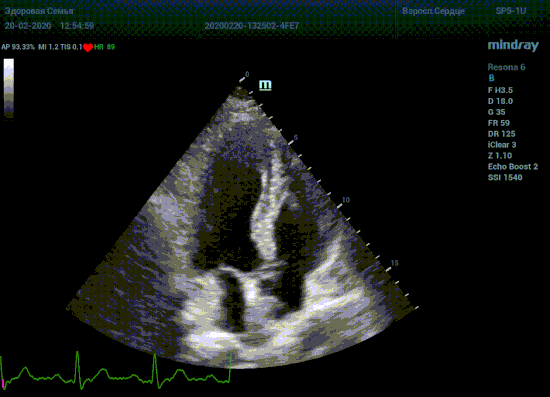

Подбор подобающей терапии и оценка её динамики на базе расчета массы миокарды рутинная задача эхокардиографии. Для измерения массы нужен кадр конца диастолы. На глазок или точно, по ЭКГ каналу, выбрать диастолу? Гипертрофия миокарда или его ремоделирование? Ремоделирование или норма? Решает каждый измеренный миллиметр, даже каждая его десятая. Лишние доли секунды приведут к началу сокращения миокарда и его утолщению, в результате -гипердиагностика.

Терапия наиболее широкая область применения, однако взрослая кардиохирургия так же важное направление современной медицины. Оперировать аортальный стеноз, или же площадь клапана достаточная? Необходимо рассчитать площадь аортального клапана по уравнению непрерывности потока. Для этого нужно измерить на зуме выносящий тракт левого желудочка (LVOT) в середине систолы. Будем угадывать момент или возьмем середину Т зубца по ЭКГ? Доверимся интуиции при определении показаний к оперативному лечению или науке?

Детская кардиохирургия не исключение. Наиболее актуальная проблема — это дефекты межпредсердной и межжелудочковой перегородок, а также открытый артериальный проток. Не верная оценка гемодинамической значимости приведет к перегрузке правых отделов сердца и ряду осложнений, в случае если не прооперировать вовремя. Отправлять маленького ребенка под нож или подождать пока дефект перегородки зарастет сам? Ждем осложнений или ждать безопасно? На эти вопросы ответит Qp/Qs соотношение, рассчитанное методом эхокардиографии. Для этого необходимо рассчитать ударные объемы выносящих трактов желудочков, опять же на середине систолы – середине Т–зубца ЭКГ.